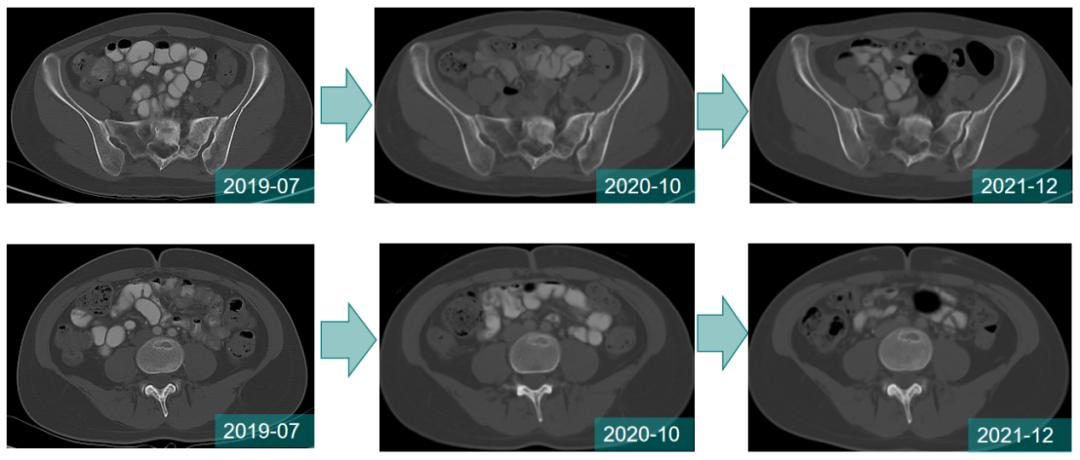

2周期治疗后腰骶部疼痛明显缓解;治疗期间每2周期评估疗效SD。

至今,骨转移病灶稳定,未出现新发病灶。